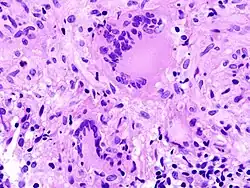

• TOUTON-Riesenzelle - Schaumzellen, bei denen um eine kleine schaumfreie Insel mehrere Kerne ringförmig angeordnet sind, Vorkommen z.B. bei juveniler Xanthogranulomatose, siehe Abb.

Fremdkörper-Riesenzellen bei Aspirationspneumonie, Autopsiepräparat, H&E.